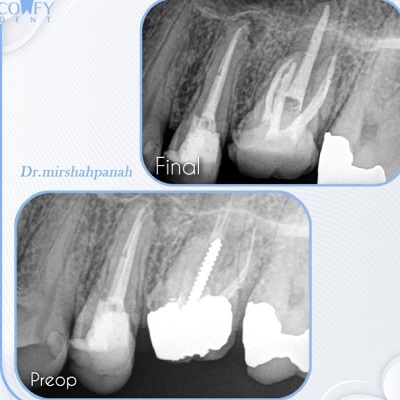

دکتر مصطفی میرشاه پناه

دکتر مصطفی میرشاهپناه، متخصص ایمپلنت و زیبایی دندان، با سالها تجربه موفق در منطقه نیاوران تهران مشغول ارائه خدمات حرفهای دندانپزشکی است. از جمله خدمات تخصصی ایشان میتوان به کاشت ایمپلنت، لمینت و کامپوزیت دندان، جرمگیری و ترمیم زیبایی لبخند اشاره کرد.